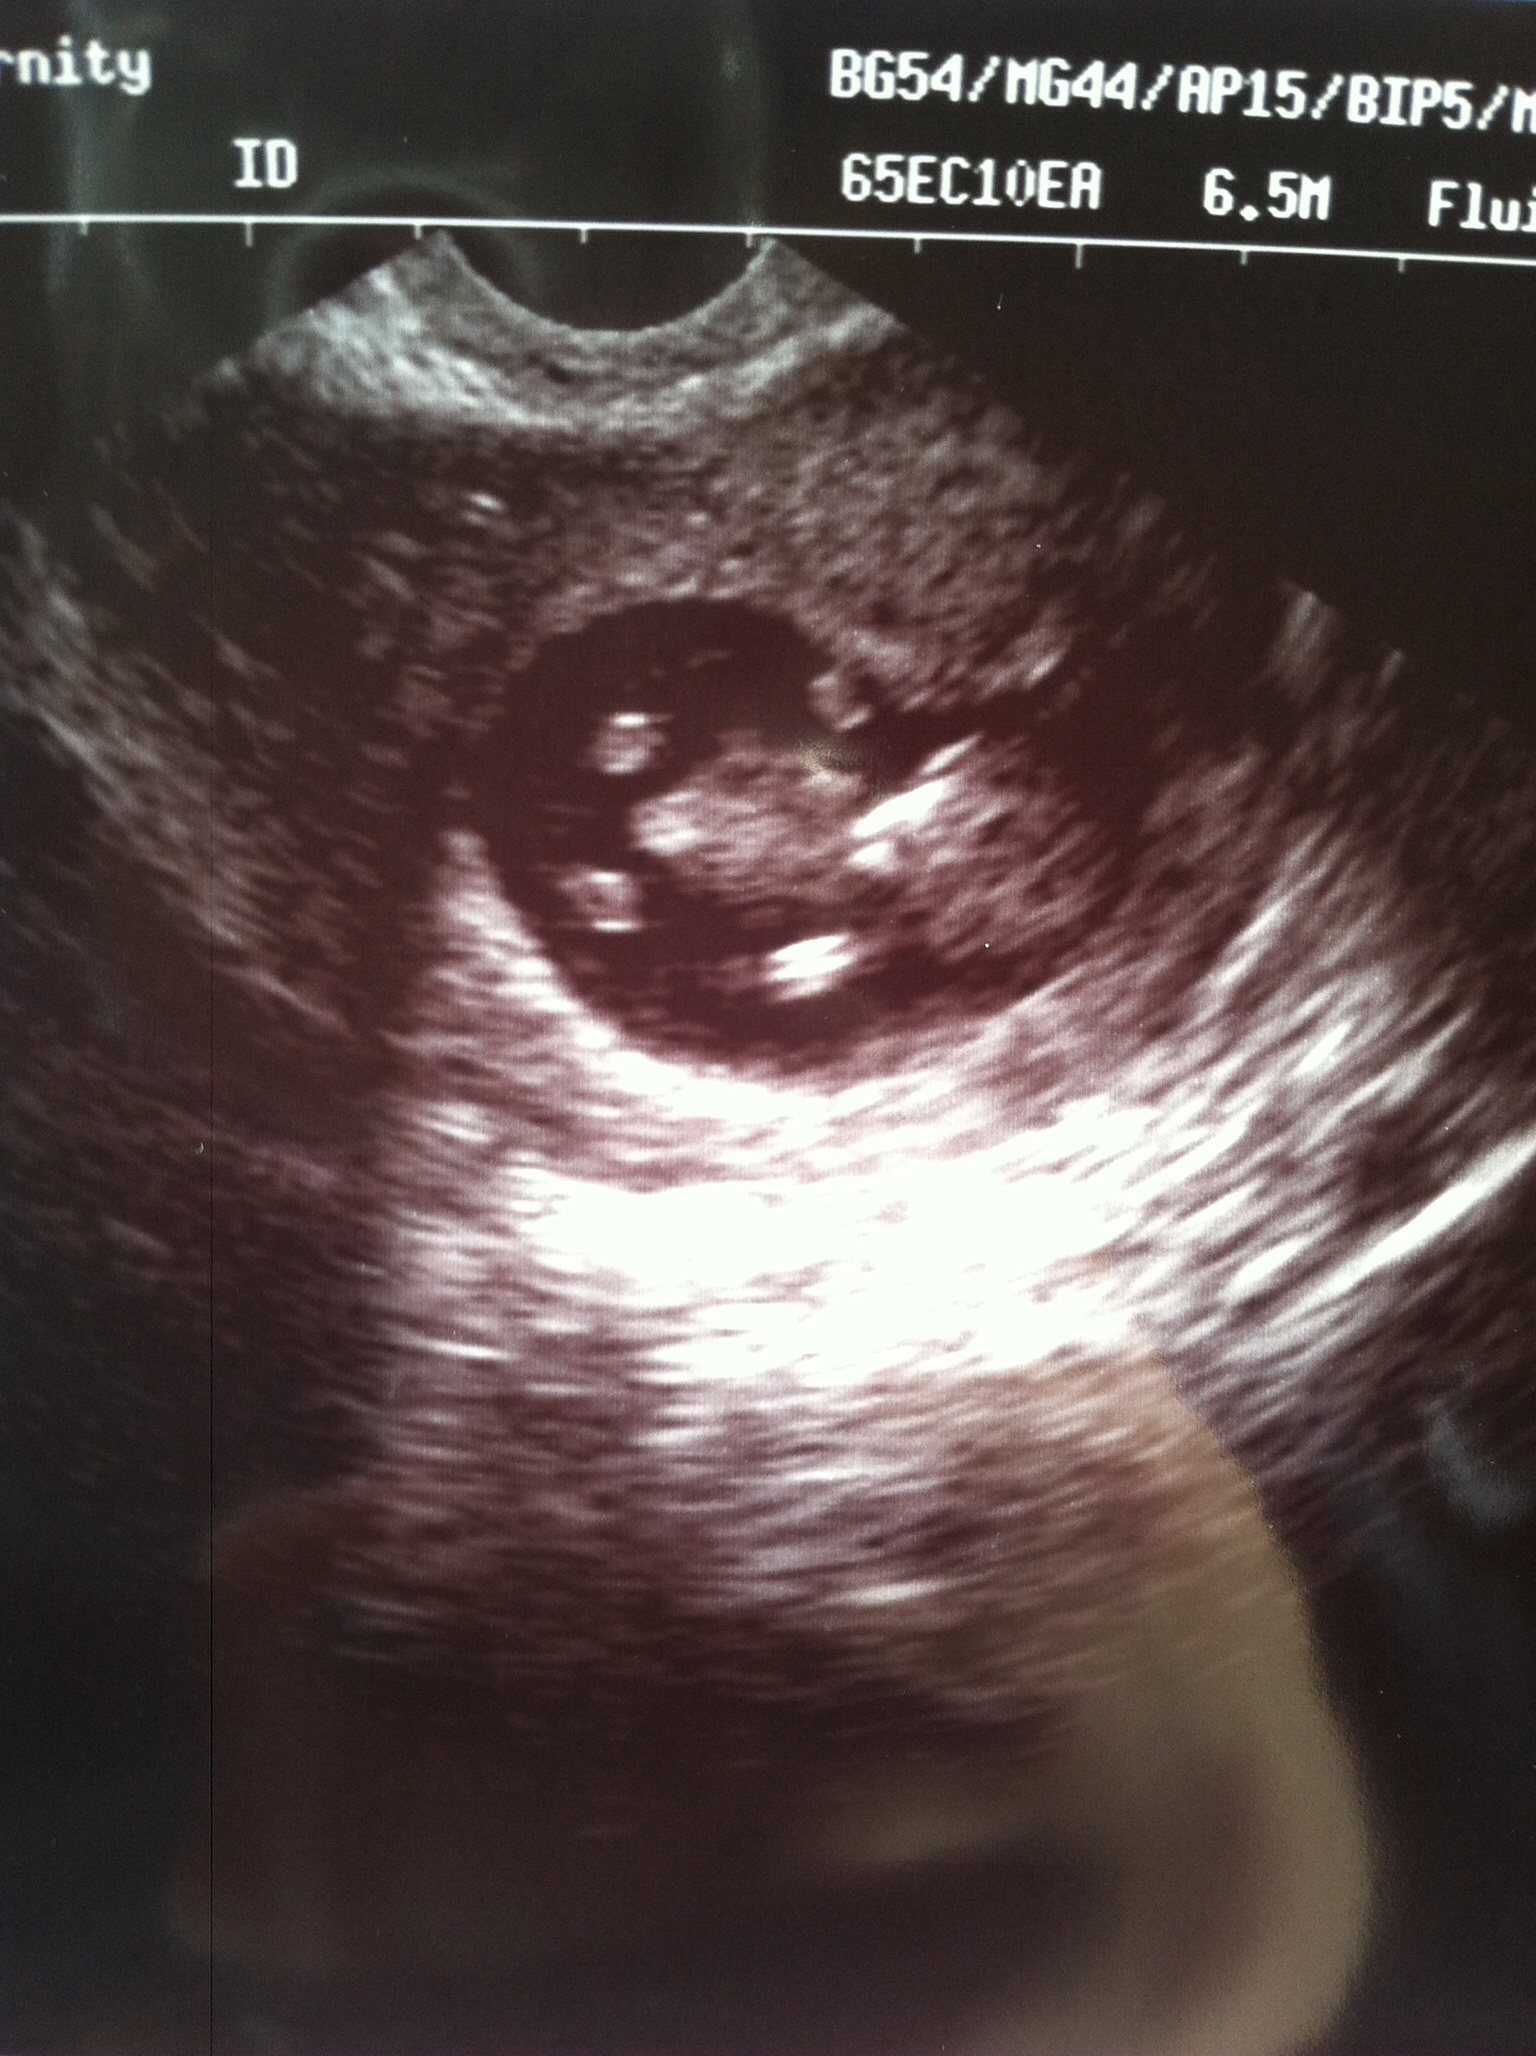

Measuring at 10wks1day. I got to see him move! It was awesome. NT scan in two weeks and follow up two weeks after that. Had a blood draw today and the girl was africkinmazing! Like seriously amazeballs! Today was still transvaginal, next time will be abdominal.